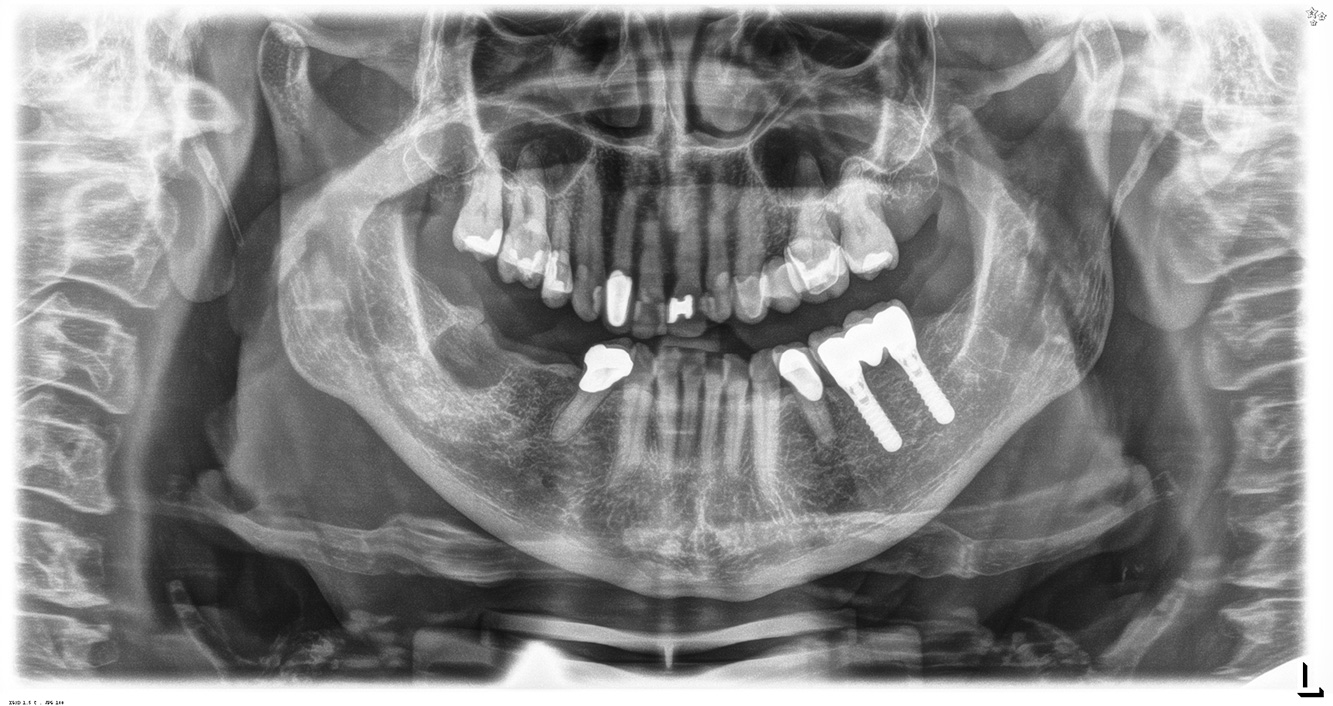

Die 68-jährige Patientin hat keine zahnmedizinisch relevanten allgemeingesundheitlichen Vorerkrankungen oder Medikation, auch aus dem Lebensstil ergibt sich kein besonderes Risiko. Die Patientin hat zwei Implantate (3. Quadrant, seit fünf Jahren) sowie eine parodontale Vorerkrankung (Parodontitis Stadium IV, Grad B) mit Zahnverlust. Derzeit zeigen sich stabile parodontale Verhältnisse. Für die Prophylaxesitzung ergeben sich vier Empfehlungen in den Bereichen Anamnese/Befund, Motivation/Instruktion, der Wahl der geeigneten Instrumente und für Resümee/Folgetermin.